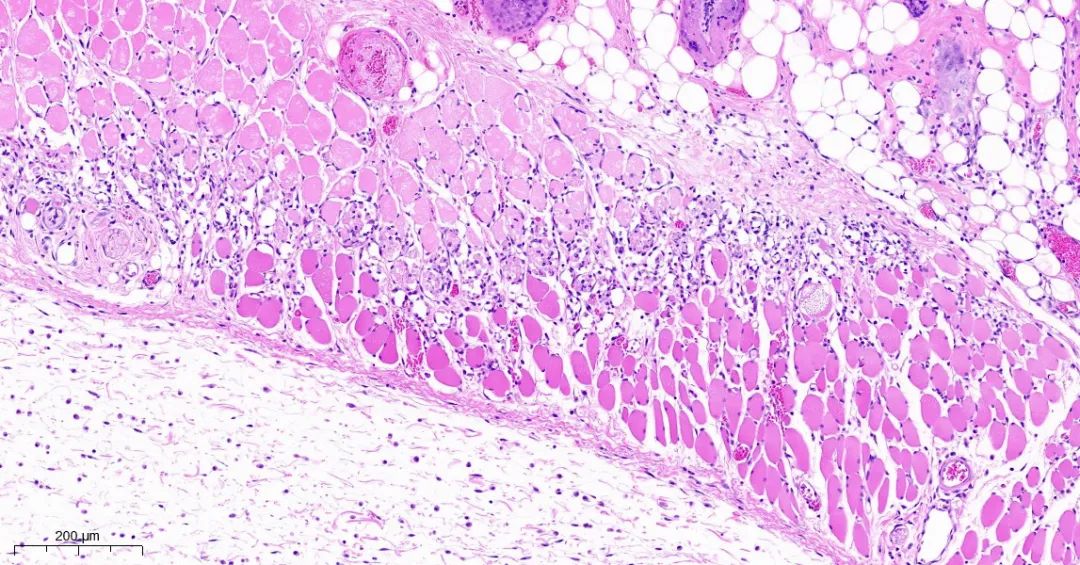

取正常对照组及模型组大鼠背部皮肤标本,常规固定,石蜡切片,HE染色,观察皮肤组织学变化。

模型1组皮组织切片对比